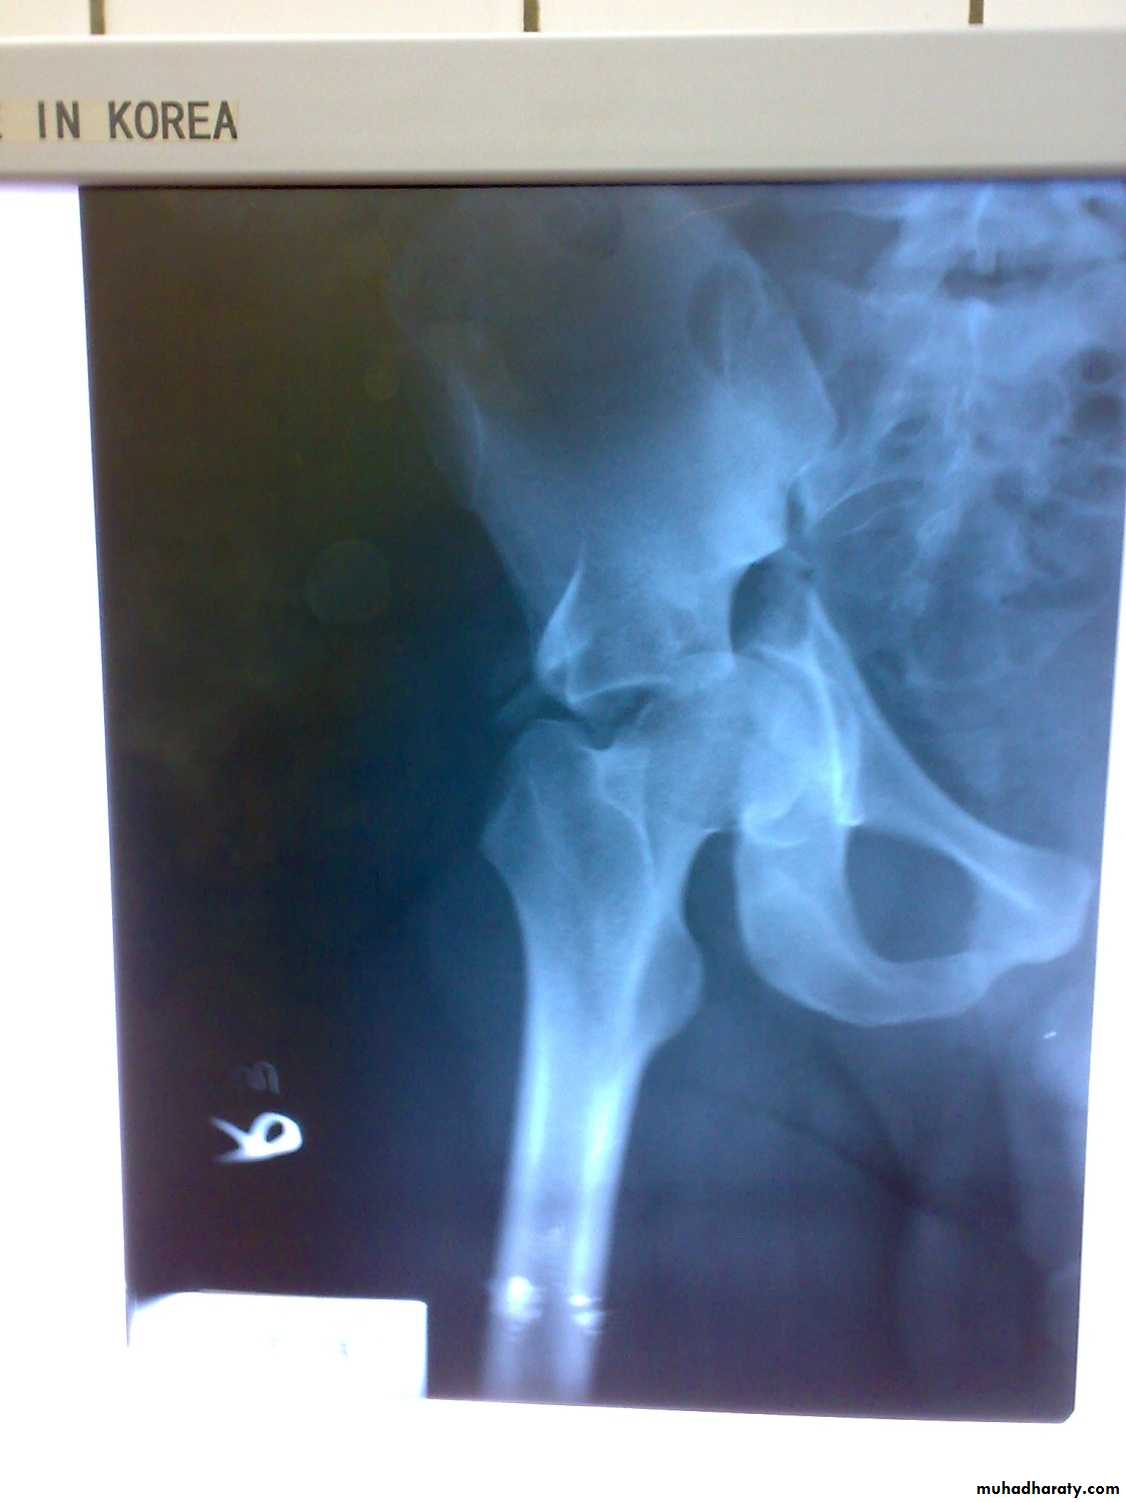

Fracture acetabulum

Fractures of the acetabulum occur when the head of the femur is driven into the pelvis.

This is caused either by a blow on the side (as in a fall from a height or road traffic accident ) or by a blow on the front of the knee, usually in a dashboard injury when the femur also may be fractured.

There is usually history of a severe injury; associated fractures are not uncommon and may divert the attention from the more urgent pelvic injuries. Whenever a fractured femur, a severe knee injury or a fractured calcaneum is diagnosed, the hips also should be x-rayed. The patient may be severely shocked. There may be bruising around the hip and the limb may lie in internal rotation (if the hip is dislocated).

Neurological examination is important, testing the function of the sciatic, femoral and obturator . Several X-ray views of the hip are needed to visualize the fracture accurately. CT scans are particularly helpful if surgical reconstruction is planned.